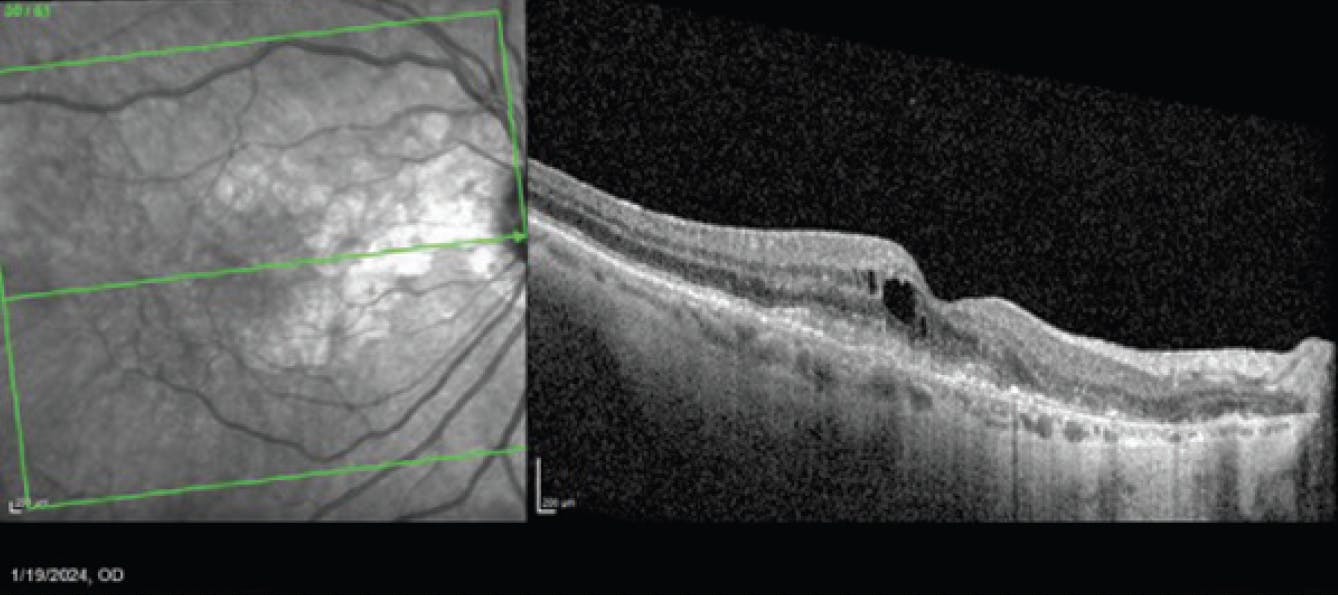

During a January 2024 visit, after 2 monthly injections of avancincaptad pegol, the patient complained of worsening vision OD. On OCT, she was found to have new cystoid macular edema, subretinal fluid, and subretinal hyperreflective material (Figure 4). She was diagnosed with new onset wet AMD and was treated with bevacizumab (Avastin). BCVA at this visit was 20/40. She returned a month later for follow-up, at which time the anatomy had improved, but BCVA was still 20/40 (Figure 5). A second bevacizumab injection was administered.

Figure 4. In January 2024, OCT (right) showed cystoid macular edema, subretinal fluid, and subretinal hyperreflective material consistent with wet AMD.